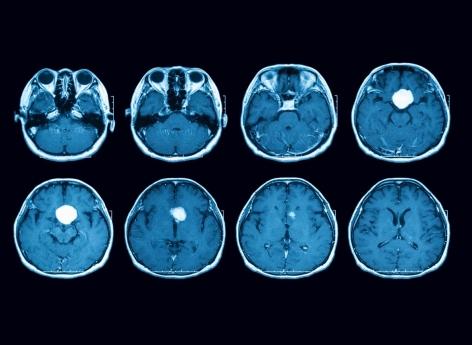

- Un scanner a révélé qu'il s'agissait d'un glioblastome multiforme, une forme agressive de tumeur au cerveau.

"C’est arrivé très soudainement, poursuit Jane. Il s’est rendu chez le médecin, et on lui a dit qu’il avait peut-être eu une attaque. Après un scanner, les médecins ont alors découvert une masse dans son cerveau".

Une tumeur cérébrale fréquente et agressive

La tumeur dont souffre Steve Dixon est un glioblastome multiforme (GBM), une tumeur primitive du cerveau. Il s’agit de la forme de cancer cérébral la plus fréquente et le plus agressive. En France, environ 5 000 cas de GBM sont diagnostiqués chaque année, avec un taux de survie faible estimé à 15 mois. Et ce, malgré un traitement combinant chirurgie intracrânienne et séances de radiothérapie et de chimiothérapie.